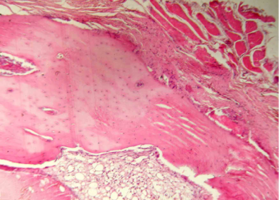

Репаративные процессы на 14 сутки после пластики костного дефекта смесью лиофилизированной аллоспонгиозы и ГАП 1:1.

На обзорной микрофотографии при малом увеличении (х100) видна зона вмешательства, содержащая имплантированный композит, представляющий собой смесь аллогенных спонгиозы и ГАП (рис. 2).

После проведенной предварительной деминерализации костей нижней челюсти в процессе стандартной гистологической проводки кристаллы ГАП в большинстве своем подвергаются растворению, поэтому не видны на препаратах либо видны лишь в единичных случаях.

На их месте чаще всего обнаруживаются округлой либо овальной формы пустоты в костном веществе имплантированной спонгиозы или в прилежащей к зоне пластики соединительной ткани.

Область вмешательства окружена интактной костью нижней челюсти и прилежащими соединительной и мышечной тканями.

Аллогенная спонгиоза в зоне пластики визуализируется в виде безъядерной субстанции костного строения, имеющей губчато-ячеистую структуру.

Содержит множество округлой, овальной и неправильной формы ячеек, заполненных соединительной тканью.

Костный компонент спонгиозы интенсивно окрашивается в ярко-красный (при окраске пикрофуксином по Ван Гизон) или ярко-розовый (при окраске гематоксилином и эозином) цвет.

Рис. 2. Нижняя челюсть кролика через 14 суток после остеопластики слева, смесь лиофилизированной аллоспонгиозы и ГАП 1:1.

Область пластики, заполненная имплантатом аллогенной спонгиозы, обозначена черными стрелками.

Синими стрелками указана интактная кость.

Окраска - пикрофуксин по ван Гизон, х100.